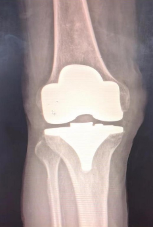

适用于晚期关节屈伸活动严重受限、畸形、生活不能自理的患者。人工关节置换术分全膝置换术和部分膝关节置换术,目前部分膝关节置换术中较为成熟的有单髁置换术。

全膝置换术:是治疗膝关节骨性关节炎的金标准,可以有效消除或缓解疼痛症状,改善患者运动功能,矫正患肢力线,提高患者生活质量。但是全膝置换术切除了前后交叉韧带、半月板,手术创伤大,术中出血量大,术后恢复慢,膝关节功能不完善,并且全膝置换术属于终极手术,截骨量多,术后翻修困难。

(全膝置换术后影像)